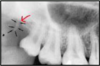

identify the anatomical structure below.

mental foramen